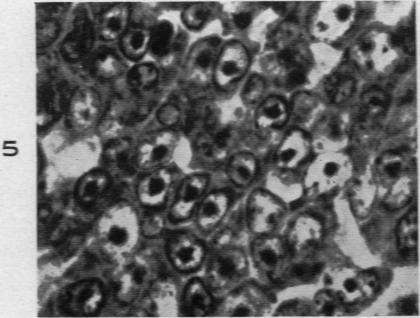

Malignant Lymphoma (So-Called Leukemia) in Dogs.

Am J Pathol. 1945 Jul;21(4):683-715.